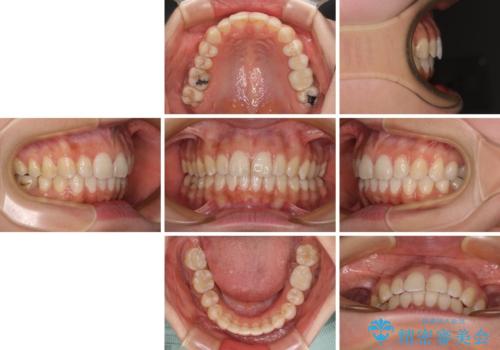

【モニター】隠れている下顎の前歯をインビザラインで改善

- 下顎の前歯が隠れていることと、デコボコを気にして来院された患者様です。

目立ちにくい装置を希望されていたため、ワイヤー装置とインビザラインを提案したところ、インビザラインを希望されました。

銀歯やムシ歯処置の必要な歯が奥歯にあり気になっていたので、矯正治療の途中でセラミッククラウンへ変更し、その後歯列を仕上げていくこととしました。

咬み合わせと目立っていた銀歯が改善され、患者様には大変満足していただきました。